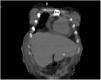

Ocho horas tras el procedimiento se inició nutrición sin resistencia a través de la sonda; la paciente presentó dolor abdominal intenso a la exploración, sin respuesta inflamatoria sistémica ni signos de irritación peritoneal. Los laboratorios no mostraron descenso de hemoglobina ni leucocitosis, únicamente trombocitopenia ya conocida (88,000 plaquetas). Al persistir con síntomas se solicitó TAC de abdomen, identificando el trayecto de la sonda a través del segmento III hepático y con el botón interno intragástrico, no se observaron datos de sangrado ni perforación (figs. 1 y 2).

Por el riesgo de sangrado y el pronóstico de la enfermedad de base, se decidió no retirar la sonda. La paciente permaneció estable y sin dolor, por lo que una semana después se realizó una TAC abdominal con contraste a través de la sonda, sin evidencia de fugas y con adecuado paso del mismo hacia la cámara gástrica (fig. 3).